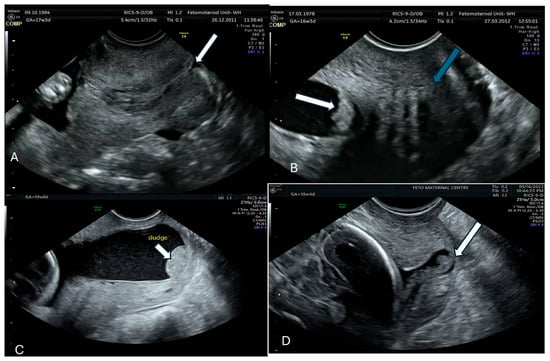

2. Amniotic Fluid (AF) Sludge and Its Constitution

3. Imaging for AF Sludge